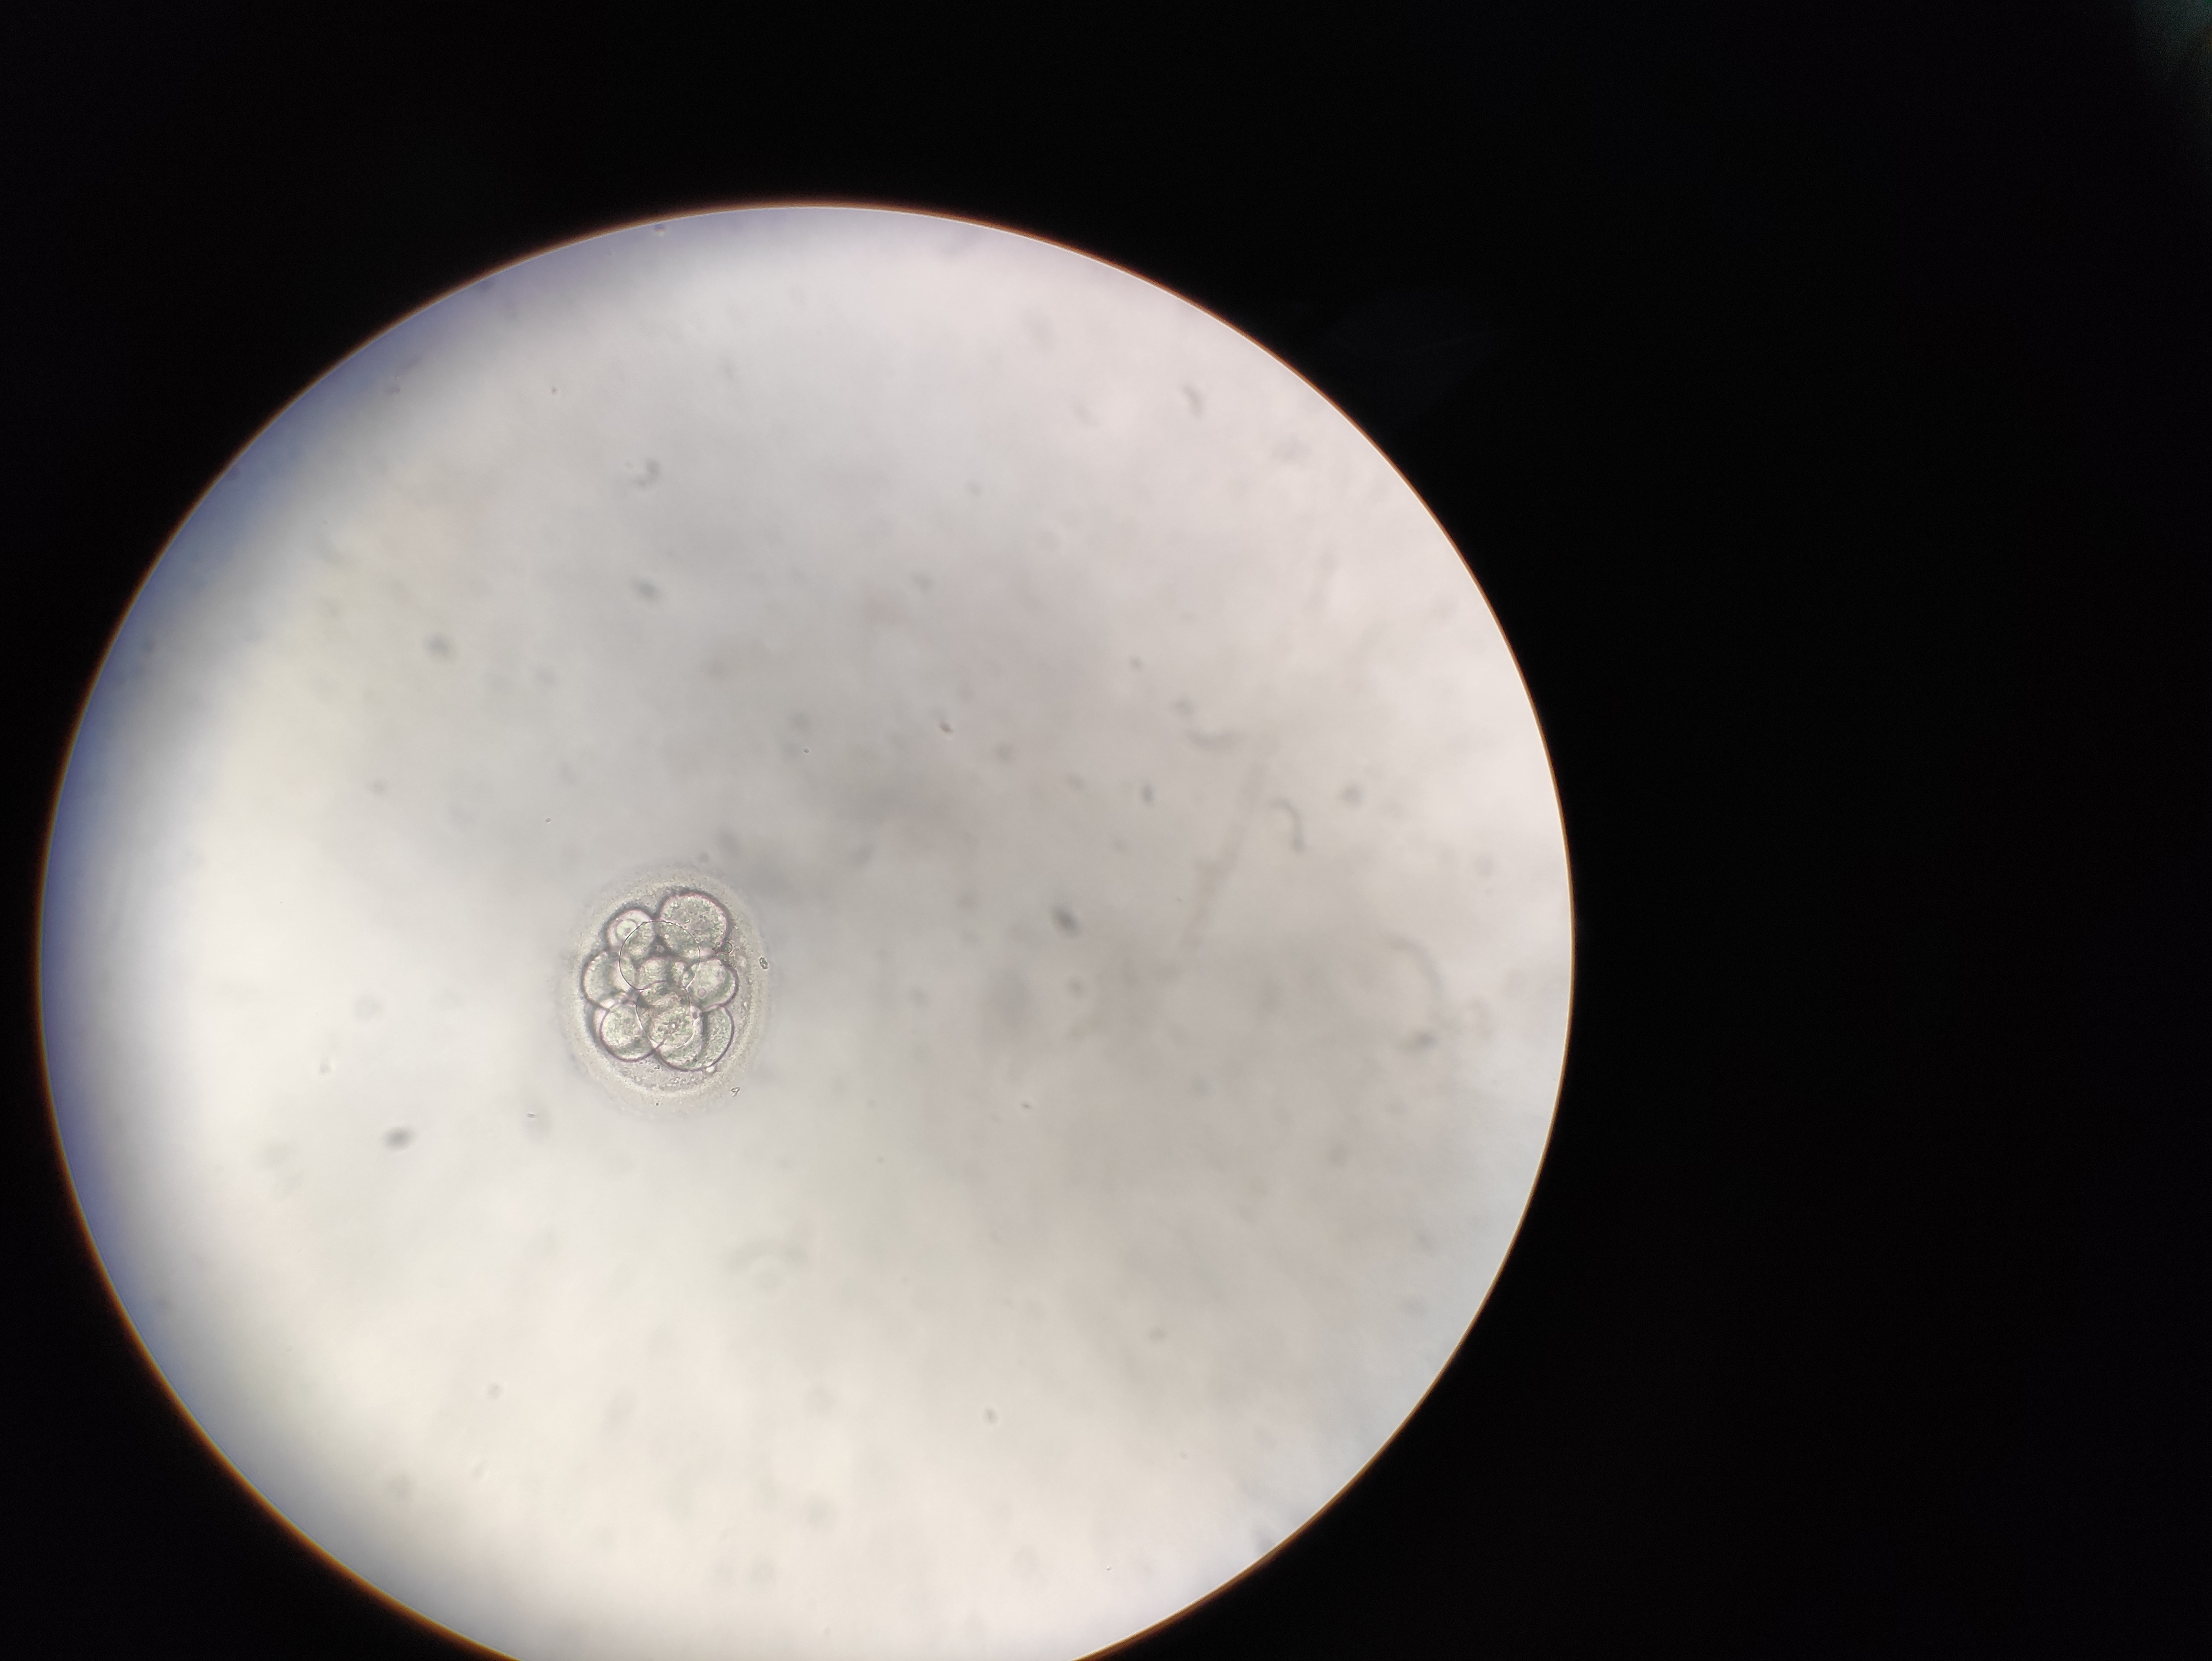

Hallo zusammen,

könnt ihr eine Bewertung zum Embryo abgeben

Embryo Bewertung